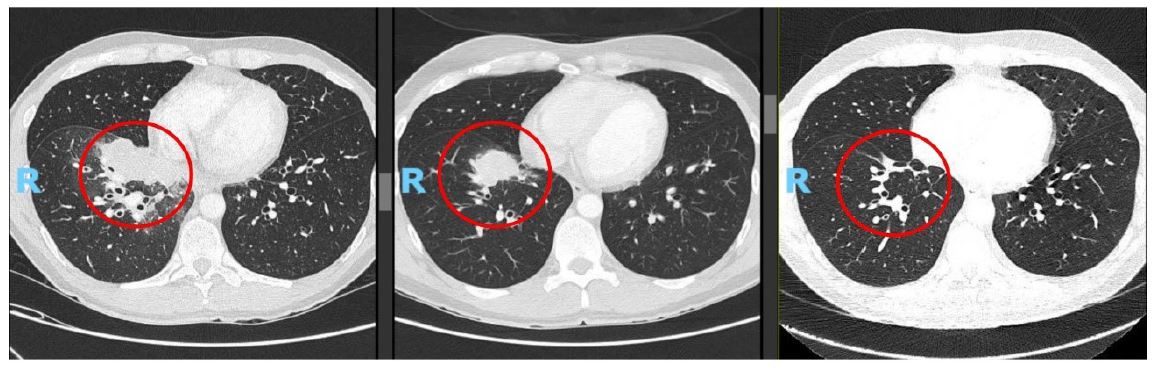

Given persistent respiratory symptoms without evidence of infection, a chest Computed Tomography (CT) scan was conducted, revealing a solid lesion in the right lower lobe suggestive of a primary tumor, accompanied by bilateral hilar lymphadenopathies. Subsequent Positron Emission Tomography-Computed Tomography (PET)-CT demonstrated elevated metabolic activity in the pulmonary lesion, bilateral hilar, cervical, mediastinal, and left inguinal lymphadenopathies, and a probable metastatic left scrotal lymph node (Figure 2).

Figure 2: The left image presents a CT scan revealing a right testicular nodule, while the right image shows the corresponding PET scan, which exhibits increased metabolic uptake at this site, consistent with malignancy.

At the first reassessment after four cycles of selpercatinib, a response was observed, marked by a significant reduction in tumor mass and disease stability confirmed by subsequent imaging (Figures 4 & 5).

Figure 4: The left image depicts the lung lesion at diagnosis (May 2023); the central image shows the lesion prior to selpercatinib initiation (January 2024); and the right image illustrates the lesion after 13 cycles of selpercatinib (January 2025), demonstrating a near-complete response.